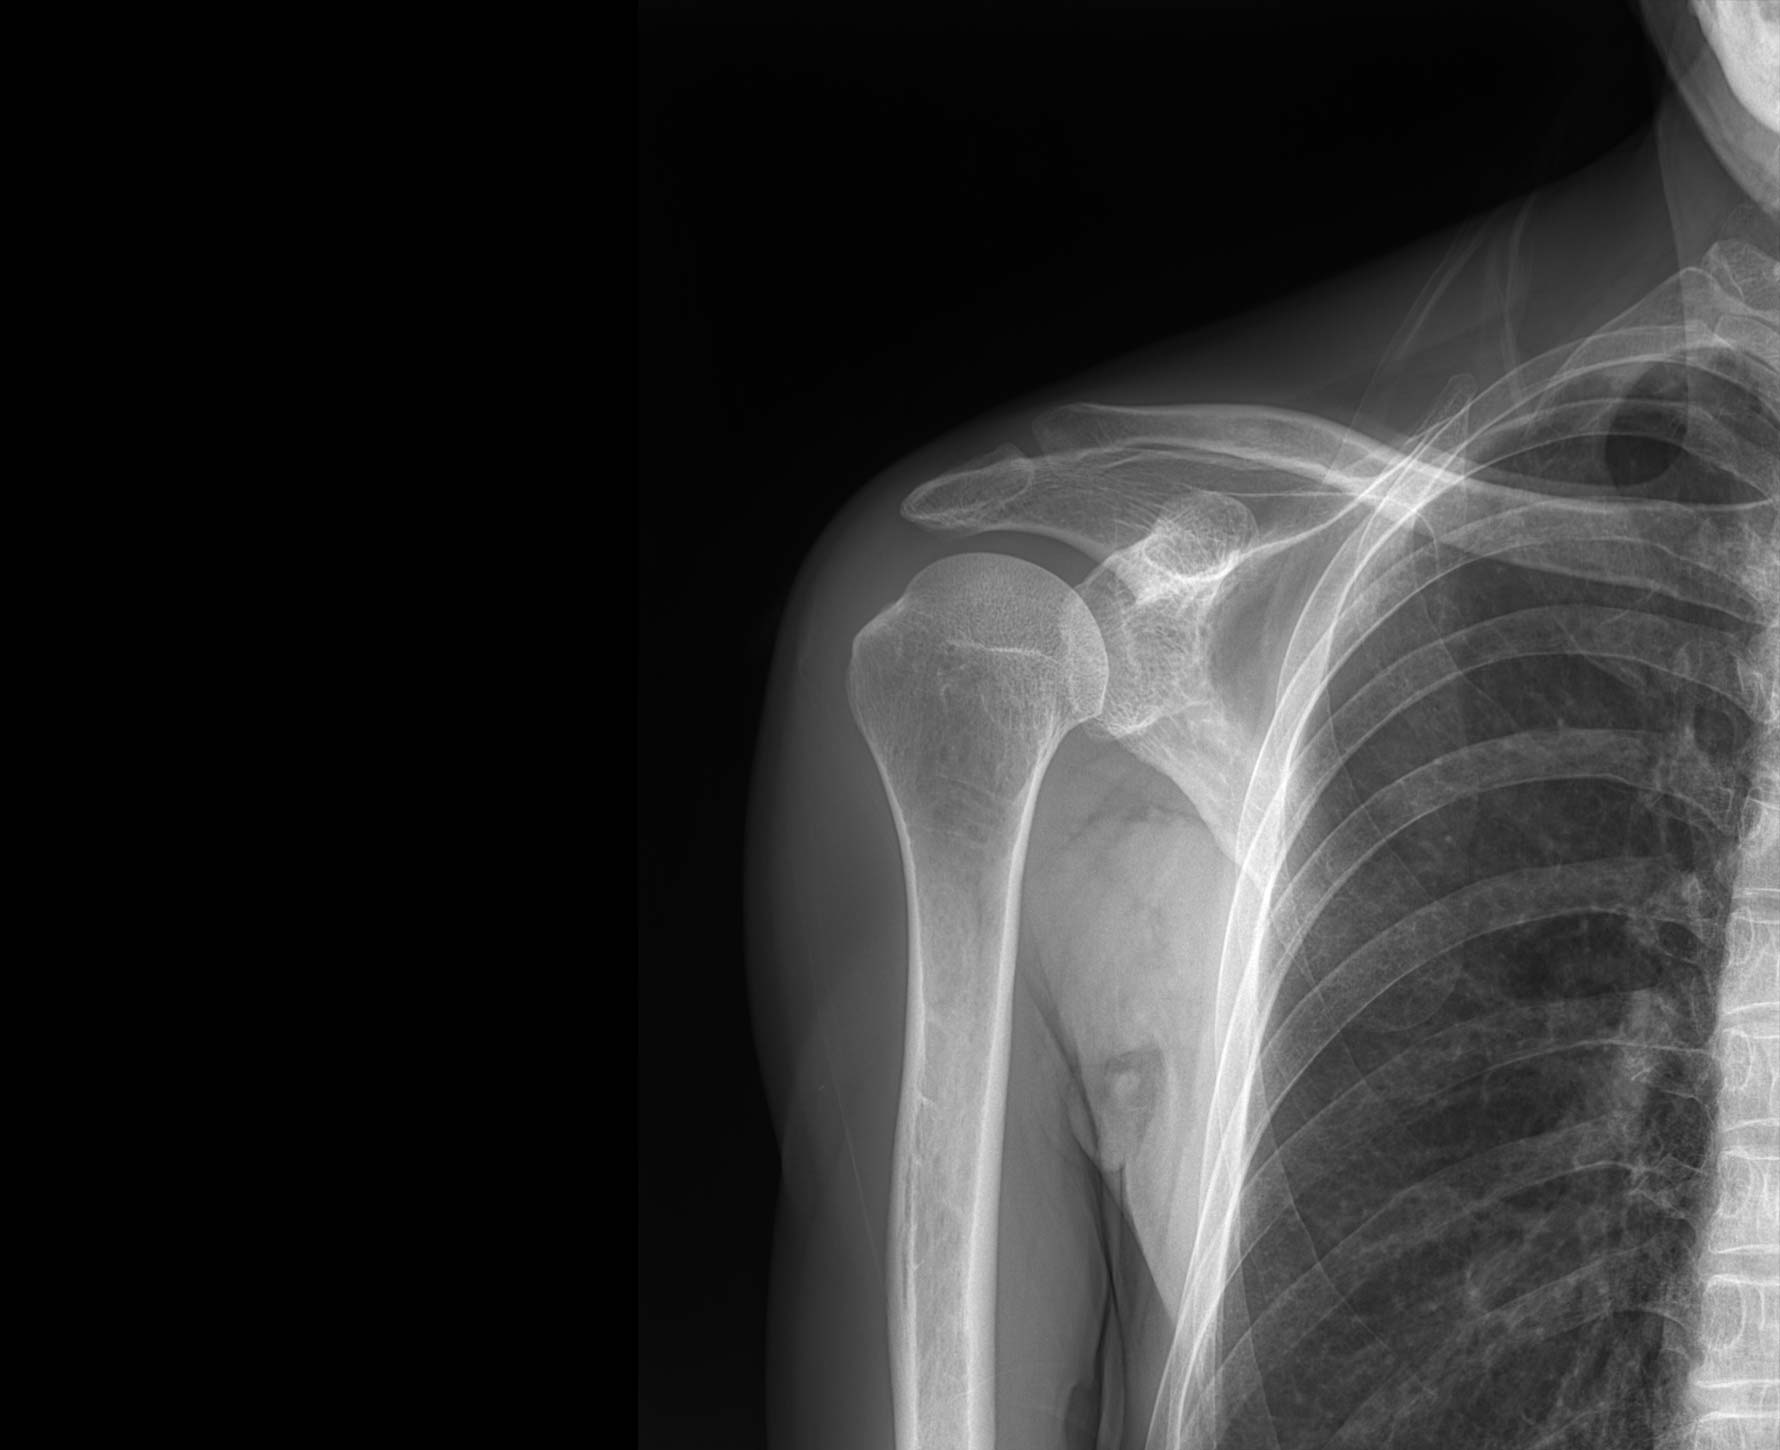

• 拍片

适用于全身各部位摄影

(常规摄影和特殊摄影)

临床图像